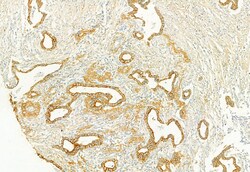

PLCE1 Polyclonal Antibody, Invitrogen™

Antibody detects endogenous levels of total PLCE1.

| Immunocytochemistry, Immunohistochemistry (Paraffin), Western Blot | |

| A synthesized peptide derived from human PLCE1(Accession Q9P212), corresponding to amino acid residues R2267-Q2302. | |